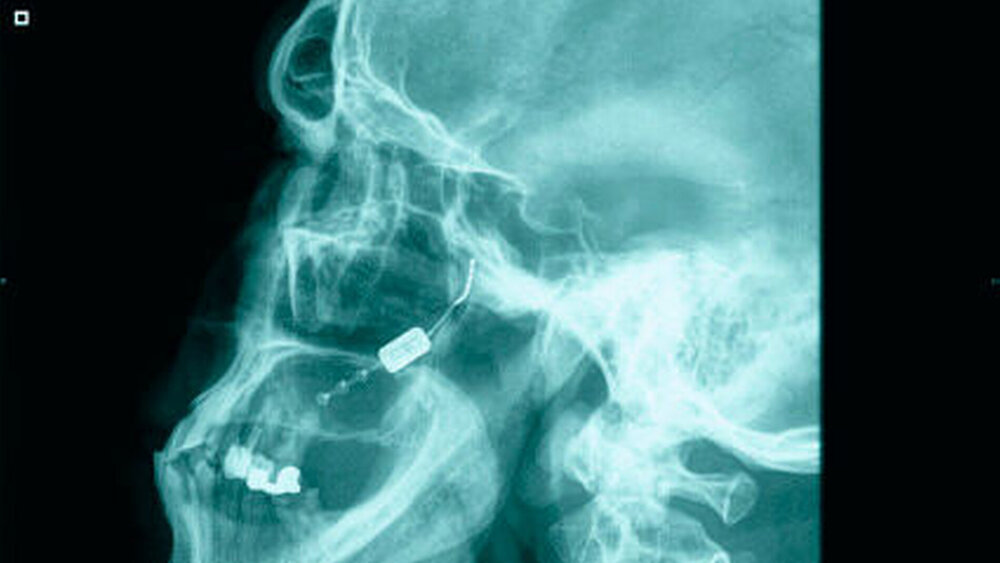

Ausschluss anderer Ursachen via Bildgebung

Diagnostisch wegweisend sind die Anamnese sowie die klinische Untersuchung. Eine Labordiagnostik sowie Bildgebung ist nicht primär zur Diagnosestellung, jedoch zum Ausschluss anderer Ursachen der Beschwerden wichtig.

Auszuschließen sind insbesondere ein Hirntumor, eine arteriovenöse Malformation, eine Karotisdissektion sowie ein Hirninfarkt und entzündliche Plaques. Im Rahmen der Erstdiagnostik werden daher in aller Regel eine kranielle Computertomografie, eine Kernspintomografie und gegebenenfalls auch eine Liquoruntersuchung veranlasst.

Bei ansonsten therapieresistenten Patienten mit chronischem Verlauf sind außerdem operative Verfahren zu erwägen. Ein Standardverfahren gibt es jedoch bislang nicht und ganz generell sind operative Eingriffe entsprechend der Leitlinien nur in „abso- luten Ausnahmefällen“ gerechtfertigt. Die Ursache hierfür liegt in der nicht unerheb- lichen Gefahr, durch die Maßnahmen eine zusätzliche und dann iatrogen verursachte Neuralgie des Nervus trigeminus oder eine Anaesthesia dolorosa hervorzurufen.

Als neues vielversprechendes Verfahren nennt die DMKG aber die elektrische Stimulation des großen Hinterhauptnervs. Erprobt wird auch die Tiefenhirnstimulation des Hypothalamus. Bei beiden Verfahren gibt es Belege für eine initiale Besserung, allerdings wurde jeweils auch eine sekundäre Verschlechterung gesehen. Entsprechend den Angaben in den Leitlinien gibt es nach derzeitiger Kenntnis eine 50-prozentige Chance, mittels solcher Verfahren eine Besserung der Klinik zu erwirken.